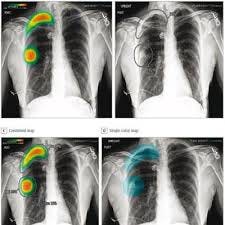

I began thinking about this when I read about an MIT and Harvard research study on the relative performance of unaided human radiologists, AI-based radiological image analysis systems, and humans and AI working collaboratively on image recognition tasks. The conventional wisdom is that the ideal situation was to have radiologists working collaboratively with AI, but it was wrong in this study. AI generally did better than unaided human radiologists, and unaided humans did better than human radiologists who reviewed AI diagnoses of the image. Radiologists working with AI also took more time to come to a conclusion than those who didn’t have an AI prediction—so much for a productivity increase with AI.

One of the authors’ possible explanations for these results is that human physicians don’t really understand how AI makes its decisions. And that’s not surprising—it’s really hard. The AI systems for radiology employ complex deep learning models, and it’s very difficult to interpret how they come to a prediction. Another study of three groups of radiologists addresses this issue—the researchers noted, “This opacity resulted in professionals experiencing increased uncertainty because AI tool results often diverged from their initial judgment without providing underlying reasoning.” In that study, many of the radiologists dealt with that opacity by refusing to adopt the AI models’ predictions. But radiologists who want to keep their jobs must somehow find a way to add value to AI technology—perhaps by sticking to the types of cases that they understand well and AI systems don’t. The number of such cases, unfortunately, is probably shrinking as AI improves.